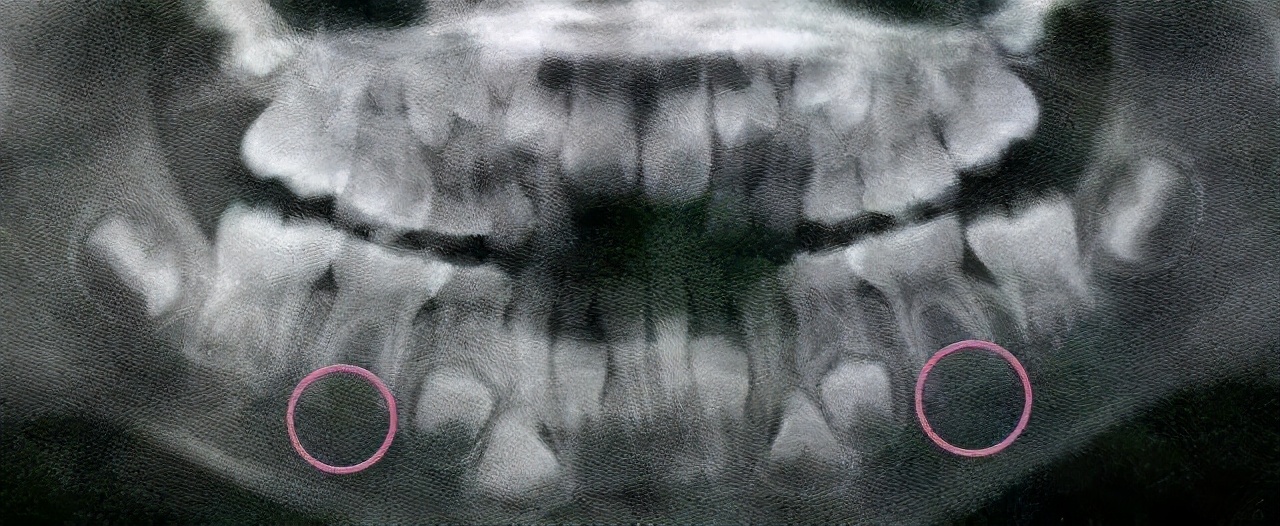

4、多生牙

有时会在两颗正常的恒牙胚间长一到两颗多生牙,多生牙不但会影响正常恒牙的顺利萌出,而且存在时间过长则易形成含牙囊肿,需及时拔除后,以便让恒牙萌出。